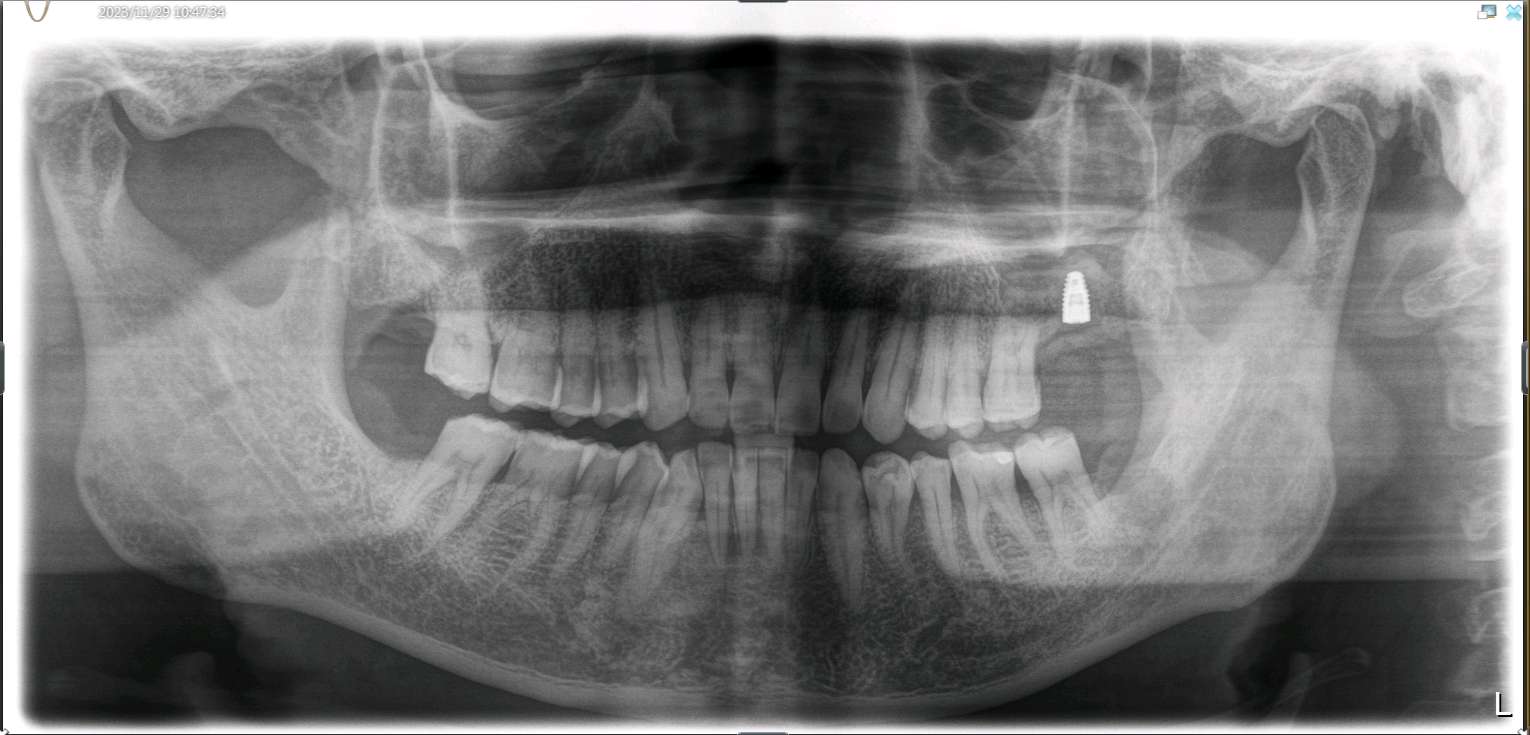

患者男,五十岁,左上后牙缺失半年。缺牙区牙槽嵴重度萎缩,无骨尖软组织的增生。邻牙见软垢结石附着,口腔卫生一般。

治疗计划1.全口龈上洁治2.种植修复(行上颌窦内提升术,植入骨粉骨膜)

患者知情同意下,抽静脉血30ml,制作 CGF ,0.1%聚维酮碘溶液口内粘膜消毒,0.5%聚维酮碘溶液口外皮肤消毒,4%盐酸阿替卡因肾上腺素注射液2.0ml浸润麻醉,牙槽嵴顶切开粘骨膜,翻瓣。见腭侧大面积骨缺损,球钻定位,先锋钻导向,骨质钻扩大种植窝,行上颌窦内提,特殊冲顶器械敲击,抬高上颌窦底部骨质和黏膜。并攻丝植入 ITI 种植系种植体4.8*8mm,上封闭螺丝,腭侧骨缺损区植 bio - oss 骨粉0.25g及 CGF ,并盖 bio - Gide 膜及 CGF 膜,严密缝合,常规医嘱,15天拆线,抗生素自备。